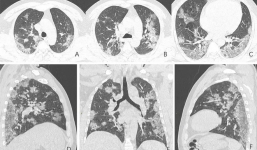

3 dấu hiệu cho thấy phổi bệnh nhân mắc Covid-19 bị tổn thương